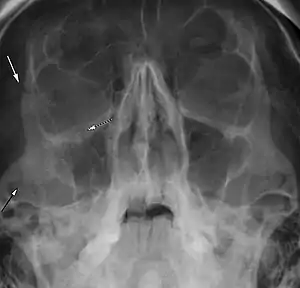

Right zygomaticomaxillary complex fracture with disruption of the lateral orbital wall, orbital floor, zygomatic arch and maxillary sinus.

The zygomaticomaxillary complex fracture, also known as a quadripod fracture, quadramalar fracture, and formerly referred to as a tripod fracture or trimalar fracture, has four components, three of which are directly related to connections between the zygoma and the face, and the fourth being the orbital floor. Its specific locations are the lateral orbital wall (at its superior junction with the zygomaticofrontal suture or its inferior junction with the zygomaticosphenoid suture at the sphenoid greater wing, separation of the maxilla and zygoma at the anterior maxilla (near the zygomaticomaxillary suture), the zygomatic arch, and the orbital floor near the infraorbital canal.